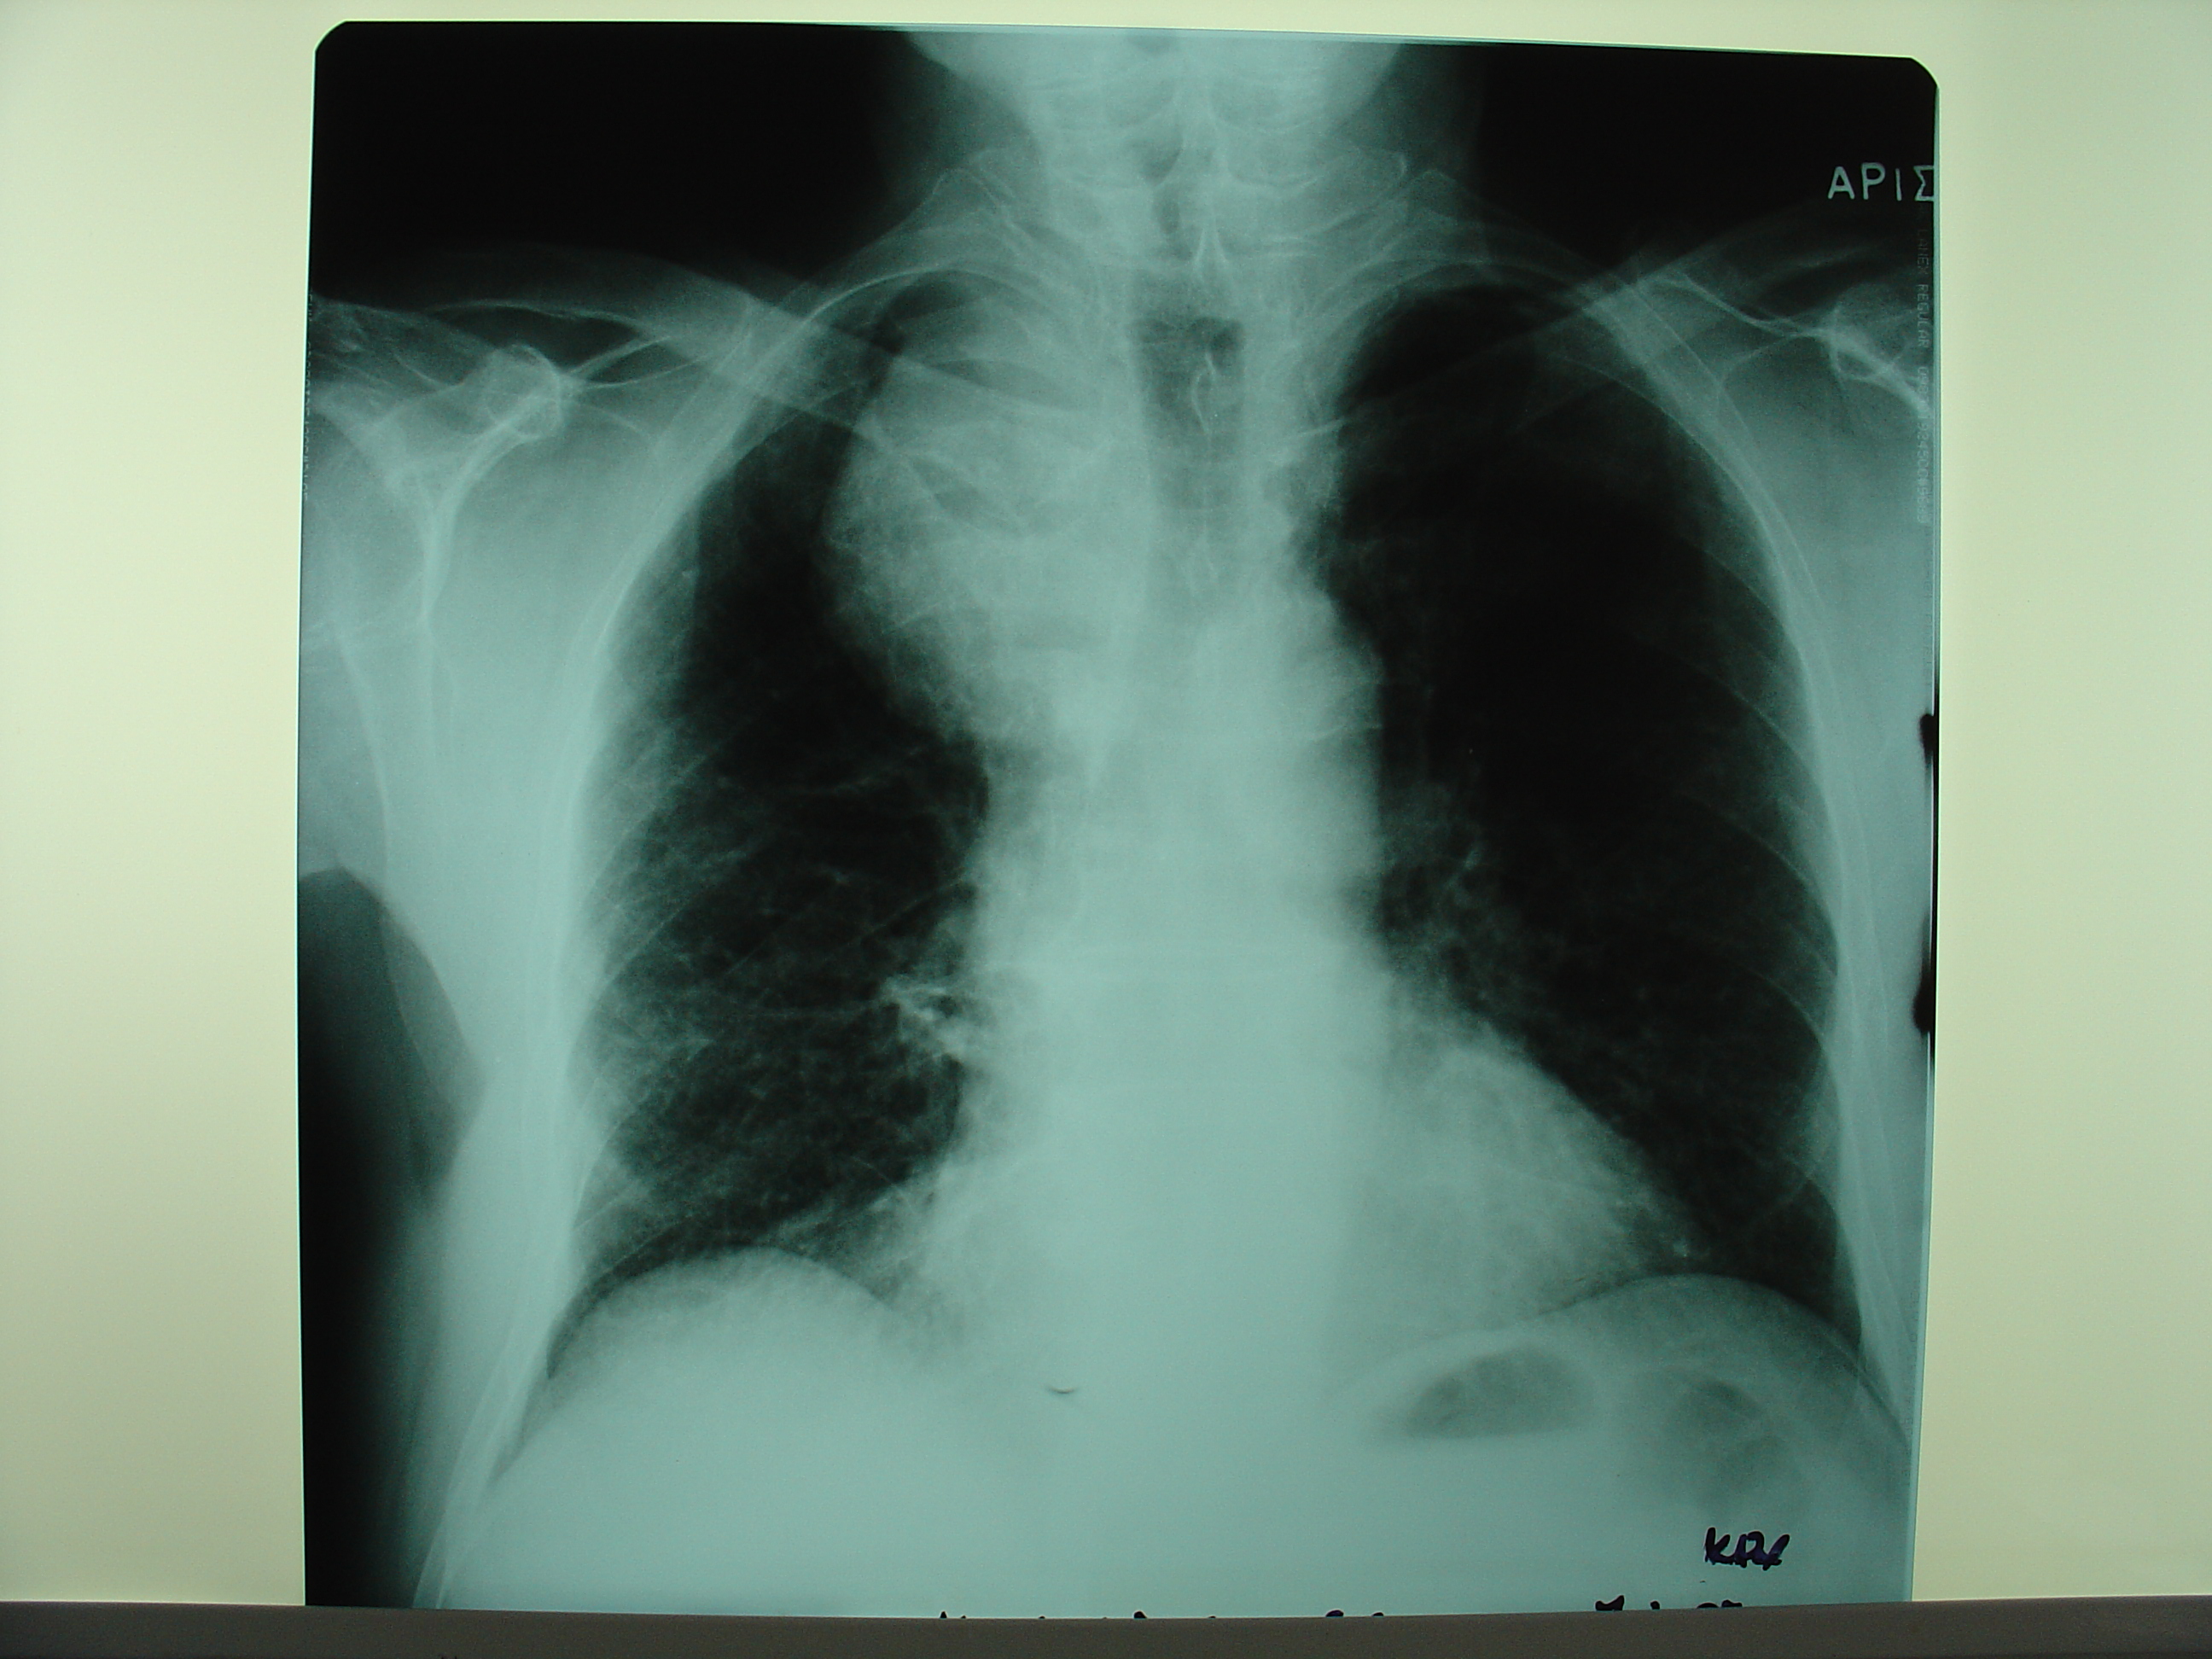

- Figure 1: Chest x-ray revealed a mass in the superior mediastinum with tracheal deviation.